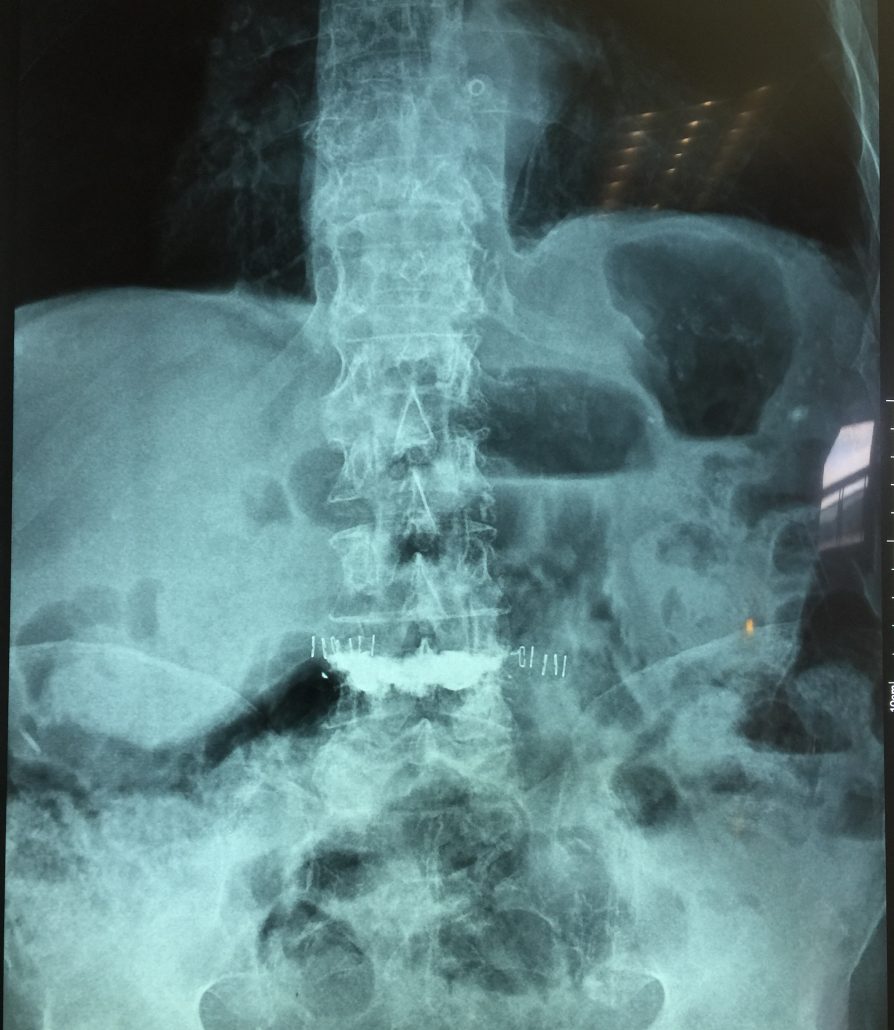

El sistema SpineJack® ha sido diseñado para la reducción anatómica de Fracturas Vertebrales por Compresión (FVC de tipo A1, A2 y A3 según la clasificación de Magerl), con o sin patologías subyacentes que afecten a la calidad del hueso, como la osteoporosis y las lesiones de origen oncológico (metástasis osteolítica o mieloma).

Diversos estudios clínicos y epidemiológicos han demostrado que existe correlación entre la deformación vertebral y problemas clínicos como la cifosis postraumática, que ha sido descrita como una de las deformidades postraumáticas potencialmente más graves. En este contexto, Vexim ha diseñado el implante SpineJack® para ofrecer al médico una solución totalmente controlada y completa para el tratamiento de las FVC, que permite primero una reducción anatómica y después una estabilización segura.